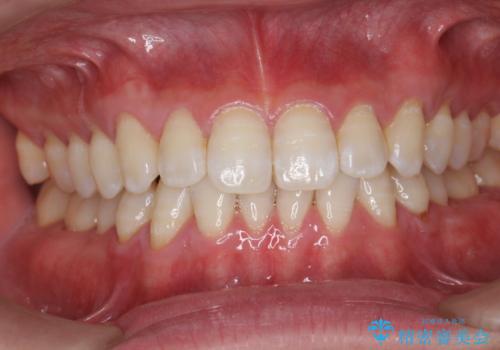

歯科衛生士によるPMTCでお口のケア

- 歯医者に来院することが久しぶりで、まずはクリーニングを希望とのことでした。コースや内容は、一番状態に合ったものでとのことだったため、PMTC60分コースを行いました。

定期的に歯科医院に来院し、PMTCを行うことが大切です。

- 歯を白くする目的の施術ではありません